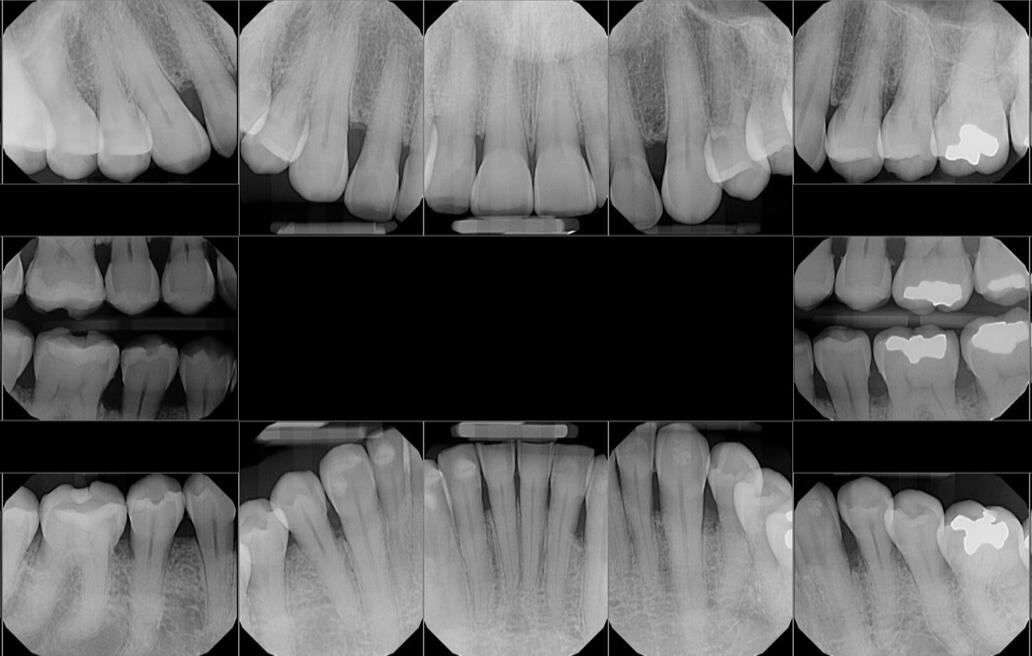

Crafted with Precision

Precision. Patience. Practice. Every treatment is handled with dedication and the kind of experience that only time can teach.

Always Learning, Always Advancing

A lifelong learner—Dr. Narendra Chetri stays up to date with the latest techniques to bring the best care to his clinic every single day.